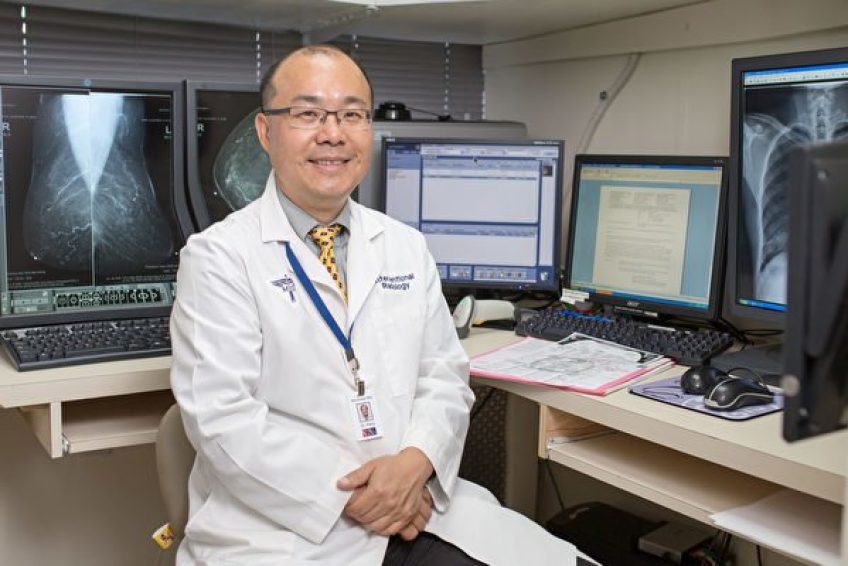

王文毅医生

诊所名称:凯辛娜医学影像中心(Kissena Radiology Associates)

所属科目:放射诊断科

凯辛娜医学影像中心的所有检查,由王文毅医生亲自操作

王医生扎实的医学教育背景及丰富的影像诊断经验,保证了检查的准确率,不易误诊和漏诊

王文毅医生1992年毕业于纽约州立大学医学院,并曾在圣卢克斯罗斯福中心医院等几大医院就职,担任总住院医师和科室主任职位。2007年,王医生决定在华人聚居地法拉盛开设诊所——凯辛娜医学影像中心(Kissena Radiology Associates)。 王医生最早萌生服务华人社区的想法,来源于父亲的遗憾。父亲最好的朋友患上乙型肝炎,多年未检查,直到最后出现肝衰竭症状才去看医生,一年不到便离开了人世。

王医师感叹,很多华人,包括自己熟悉的朋友,他们勤劳工作、照顾家庭,但对看病却非常抵触,一再拖延看医生的时间,最终造成不可挽回的健康损失。 在纽约皇后区长大的王文毅医生,从小学习勤奋努力,少年时代的他每天放学后在父亲的餐馆帮工。“皇后区的大街小巷都有我骑自行车送外卖的身影。”对这片养育自己长大的土地,个性直率的王文毅医生难以掩饰他的赤子之心,他希望以自己的专业知识帮助这里的人们更好地守护健康。

法拉盛影像科医生王文毅:

医学博士,近20年医学影像专业临床经验,曾以住院总医师身份负责培训住院医师。王医生潜心钻研,对医学影像技术运用自如,要求精益求精,对医学影像发现病灶思考全面,解读仔细。专长乳腺钼靶检查、计算机断层扫描(CT)、MRI检查(核磁共振影像)、各种X线检查等医学影像诊断技术,并擅长根据超声影像定位病灶位置,以微创穿刺技术取得病理组织,以诊断疾病。